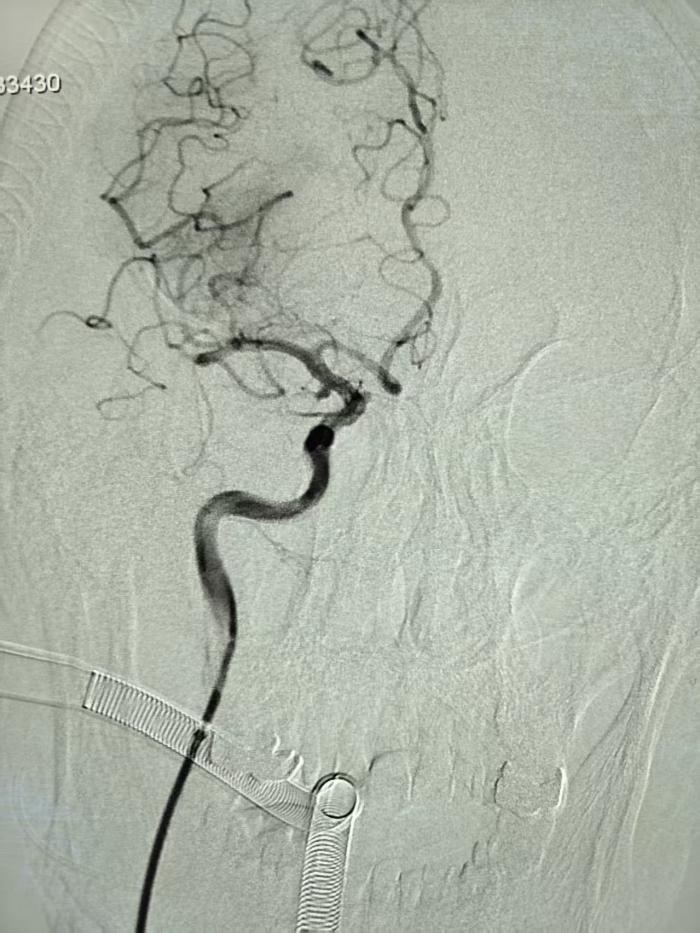

凌晨2时许,黄老先生突然瘫倒在家,左侧肢体完全瘫痪、意识模糊。120急救车抵达医院后,卒中绿色通道立即启动。头颅CTA检查揭示双重危机:右侧大脑中动脉M1段完全闭塞,同时右侧颈内动脉后交通段潜伏着一颗直径约4mm的动脉瘤。

步步惊心:三维路图引导下的“双线作战”

凌晨3:05,静脉溶栓药物注入患者体内,介入团队同步开展术前准备。面对血管严重迂曲,手术团队采用“长鞘+支撑导管+支架导管同轴技术”,利用三维血管路图精确定位。术中可见取栓支架释放后,血栓与动脉瘤相距不到2cm,主刀医生康敬源巧妙调整导管角度,以“悬空穿越”方式避开动脉瘤体,最终采取SWIM技术一次性取出多块混合型血栓,最大者4mm*2mm。

凌晨4:24,黄老先生原本闭塞的血管,顺利实现三级再通,动脉瘤完好无损。从接诊患者到完成手术,全程只用了79分钟。